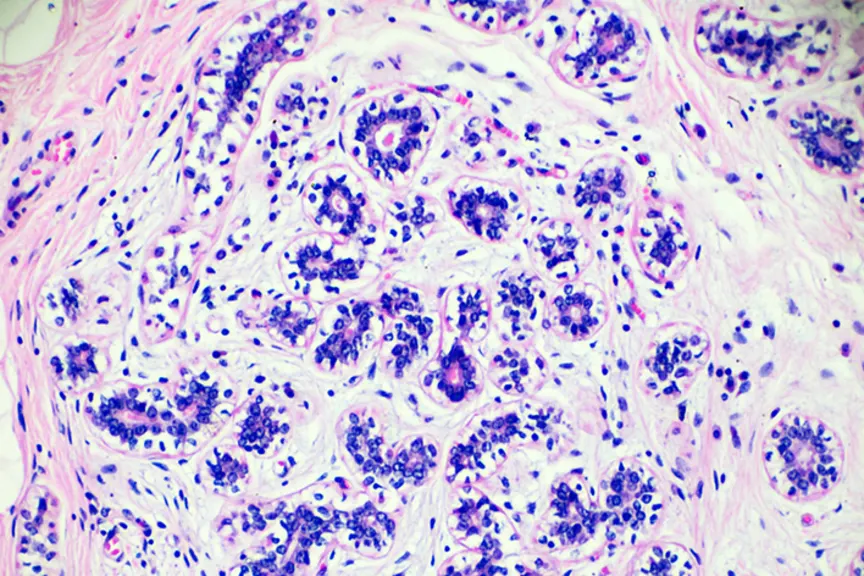

来自伦敦玛丽女王大学的研究人员使用多基因检测endpredict来评估化疗是否对患有最常见的癌症的女性有益乳腺癌(雌激素受体阳性,her2阴性),根据发表在乳腺癌研究与治疗。一般来说,医生建议化疗的妇女有很高的风险转移(当癌症扩散)。

并不是每个乳腺癌患者都被推荐化疗,但有时很难判断化疗是否有用。一般来说,医生会对患者进行基因测试,并观察肿瘤大小和分级等,以确定雌激素受体阳性乳腺癌患者的最佳治疗方案。85%的女性乳腺癌患者受雌激素受体阳性影响。